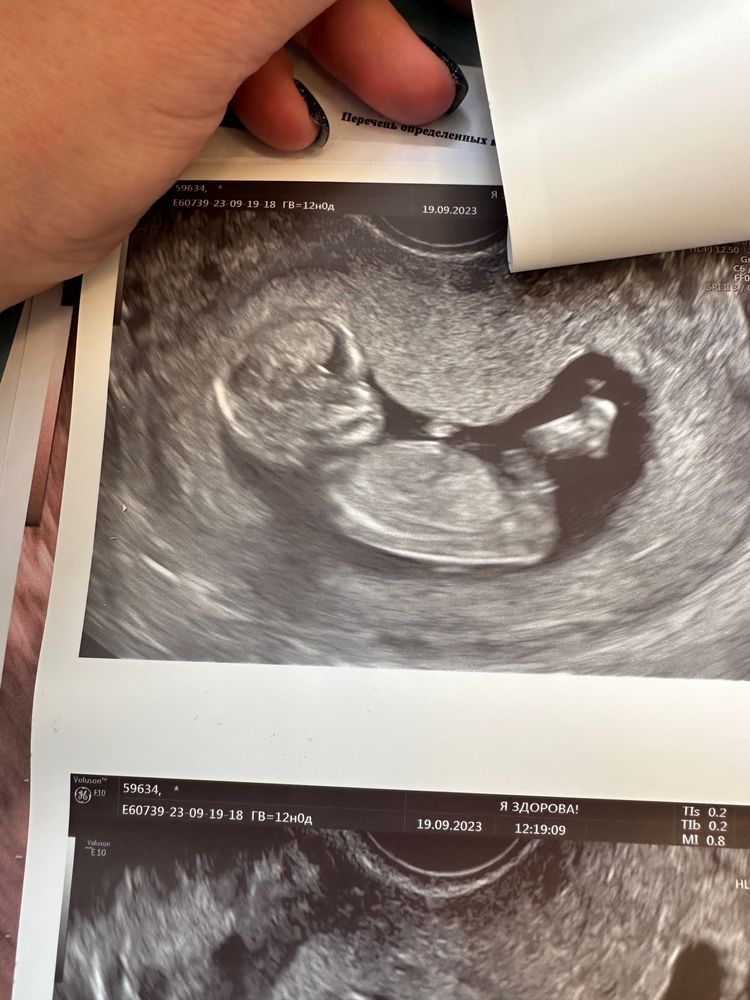

могу ошибаться, но кажется мальчишка. На первом снимке вижу стручок вроде как вверх направлен.

Татьяна, да, у девочек она идет вдоль животика вниз, а у мальчика немного вверх задрат